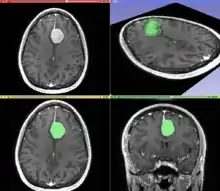

Segmentation

Segmentation is the process of partitioning an image into different meaningful segments. In medical imaging, these segments often correspond to different tissue classes, organs, pathologies, or other biologically relevant structures.[2] Medical image segmentation is made difficult by low contrast, noise, and other imaging ambiguities. Although there are many computer vision techniques for image segmentation, some have been adapted specifically for medical image computing. Below is a sampling of techniques within this field; the implementation relies on the expertise that clinicians can provide.

- Interactive Segmentation: Interactive methods are useful when clinicians can provide some information, such as a seed region or rough outline of the region to segment. An algorithm can then iteratively refine such a segmentation, with or without guidance from the clinician. Manual segmentation, using tools such as a paint brush to explicitly define the tissue class of each pixel, remains the gold standard for many imaging applications. Recently, principles from feedback control theory have been incorporated into segmentation, which give the user much greater flexibility and allow for the automatic correction of errors.[9]

- Convolutional neural networks (CNN's): The computer-assisted fully automated segmentation performance has been improved due to the advancement of machine learning models. CNN based models such as SegNet,[14] UNet,[15] ResNet,[16] AATSN,[17] Transformers[18] and GANs[19] have fastened the segmentation process. In the future, such models may replace manual segmentation due to their superior performance and speed.